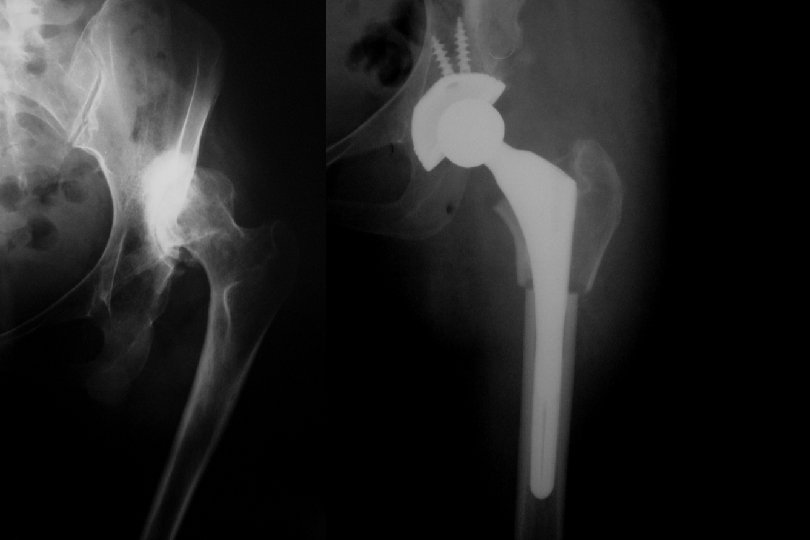

Adult • Artrodez !!! • Total Eklem Replasmanı • Genç ve aktif yaştalar • İyileştirilmiş malzemeler kullanılmalı • Hasta çok detaylı bilgilendirilmeli